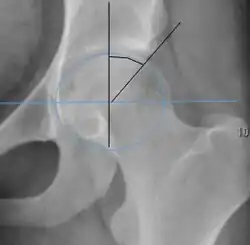

Projectional radiography ("X-ray") is often considered first line for FAI.[10] Anterior-posterior pelvis and a lateral image of the hip in question should be attained.[10] A 45-degree Dunn view is also recommended.[10][19]

| Crossing ratio |

|

Percentage of acetabular walls crossing. Normal acetabulum is oriented in anteversion. Its value ranges from 15 to 20° in the equatorial plane of the acetabulum and decreases gradually towards the acetabular roof, where normal values range from 0 to 5°. Retroversion of the upper part of the acetabulum has been related with pincer type impingement. In radiography the presence of a "crossover sign" is produced when the posterior wall of the acetabulum crosses the anterior wall before reaching the acetabular roof. It is a sign of acetabular retroversion and it has been linked with overcoverage and pincer impingement. Nevertheless, this sign has been described in 6% of the normal population. Therefore, more important than its presence is the percentage of crossing. | <20%